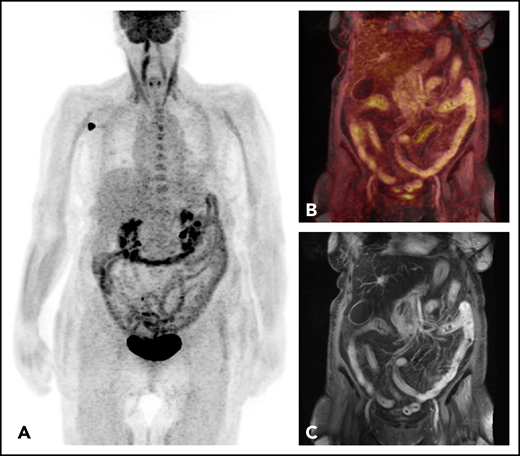

FDG-PET-MRI of a 70-year-old patient with acute intestinal GVHD. (A) Maximum intensity projection of PET and (C) the fused PET-MRI show increased FDG uptake in small and large bowel. (B) Coronary T1-weighted postcontrast MRI allows for assessment of corresponding morphological changes, including mural hyperenhancement, wall thickening, mural stratification, and the Comb sign.

On the other hand, as correctly mentioned by Assmann et al, PET does come with radiation exposure, whereas metabolic MRI does not, which might limit serial investigations in patients with GVHD. However, radiation doses resulting from PET-CT are diagnostic and rather low, and therefore only minimally add to therapeutic doses, in the frame of allogenic HSCT algorithms. Novel approaches, such as FDG-PET-MRI, further decrease radiation exposure and, at the same time, also provide additional and independent MRI-based evidence of intestinal GVHD (see figure).